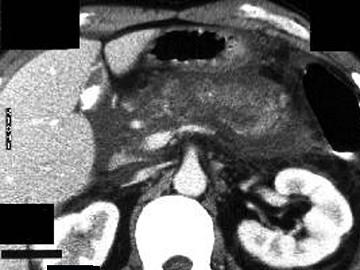

问题 女,45岁,急性上腹部持续性疼痛,程度剧烈,放射到胸背部,恶心、呕吐,白细胞计数增高,血尿淀粉酶升高,影像所见如图,最可能的诊断是 ( )

选项 A、胰腺癌 B、胰腺脓肿 C、急性出血坏死性胰腺炎 D、慢性胰腺炎 E、急性单纯性胰腺炎

答案 C